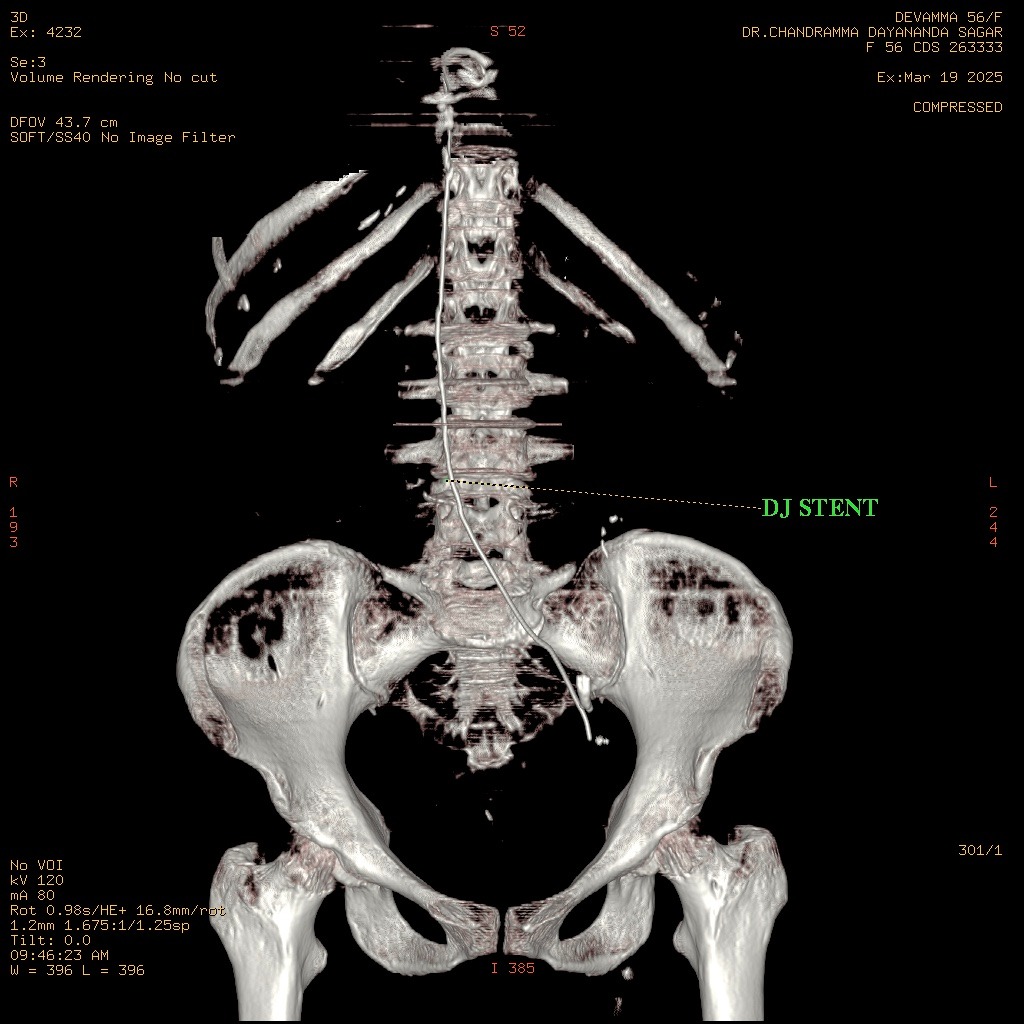

Following the easy passage of the hydrophilic wire, a 3Fr ureteric stent was passed over it. The stent advanced without resistance, but the proximal pigtail did not coil in the renal pelvis, heightening the suspicion of misplacement. An immediate post-procedure CT scan confirmed the stent's location: the distal end was correctly within the bladder, but the main body and proximal end were located outside the ureter, passing into the Inferior Vena Cava. However, further investigation with MRI of Abdomen revealed that the stent had migrated from the bladder to the left internal iliac vein and reached in the Right Atrium. The patient remained hemodynamically stable. A team meeting was sought, including the opinions of the Cardiologist, Cardiothoracic surgeon, and Urologist, and came to a conclusion that a attempt via endovascular retrieval of the stent. Initial attempts by interventional cardiology via the femoral vein to the Right Atrium failed. Successful retrieval was achieved by an alternative access via the right internal jugular vein, direct entry into the left internal iliac vein. A snare catheter was skillfully deployed to secure the distal end of the DJ stent. The stent was removed successfully without any immediate vascular complication. The patient was monitored in the MICU post-procedure. On the second day post procedure, patient developed mild hematuria and was treated conservatively, and repeat CT KUB with contrast was done, which did not show any remnant fistula.

Case Summary

DJ Stent migration into the cardiac chambers represents a catastrophe, with published literature frequently describing the need for emergency cardiothoracic surgery (e.g., sternotomy or thoracotomy) to prevent life-threatening sequelae such as arrhythmias, tricuspid valve damage, or myocardial perforation. Ureteral stent migration, particularly rare vascular displacement to the heart requires immediate diagnosis and retrieval. Our case demonstrates that a rapid, endovascular approach provides the safest template for management, setting a new standard for emergent care. Careful placement and sizing remain vital to prevent migration